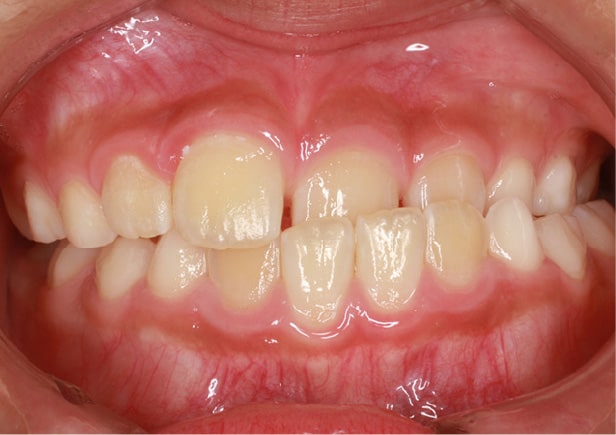

• 症例2

矯正bofore

矯正種類 ワイヤー矯正

症例 上下額叢生

治療期間 2021年12月〜2024年10月

性別/年代 男 13歳

治療費 748,000円

コメント

適切な時期に治療が開始できたので、歯並びだけでなく顎や顔貌も理想的に成長しました。歯磨きもしっかりできるようになりました。